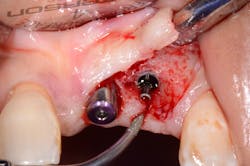

If the occlusal forces delivered to the implant-abutment-crown complex exceed the screw’s clamping ability, this may result in either its loosening (figures 1a and 1b) or, in more severe situations, fracturing of the screw (figures 2a–2c). Clinicians often indite the occlusion as being the primary culprit for the problem; however, in a number of instances, this may not be the case. The cause of screw loosening could also be due to using aftermarket parts, which do not have the precise fit of those made by the manufacturer of the implant.7